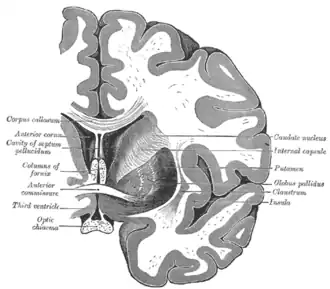

Along with the putamen, the caudate forms the dorsal striatum, which is considered a single functional structure; anatomically, it is separated by a large white-matter tract, the internal capsule, so it is sometimes also described as two structures—the medial dorsal striatum (the caudate) and the lateral dorsal striatum (the putamen). In this vein, the two are functionally distinct not because of structural differences, but merely because of the topographical distribution of function.

The caudate nuclei are near the center of the brain, sitting astride the thalamus. There is a caudate nucleus in each hemisphere of the brain. Each nucleus is C-shaped, with a wider "head" (caput in Latin) at the front, tapering to a "body" (corpus) and a "tail" (cauda). Sometimes a part of the caudate nucleus is called the "knee" (genu).[6] The caudate head receives its blood supply from the lenticulostriate artery; the tail of the caudate receives its blood supply from the anterior choroidal artery.[7]

The head and body of the caudate nucleus form part of the floor of the anterior horn of the lateral ventricle. The body travels briefly towards the back of the head; the tail then curves back toward the anterior, forming the roof of the inferior horn of the lateral ventricle. This means that a coronal section (on a plane parallel to the face) that cuts through the tail will also cross the body and head of the caudate nucleus.